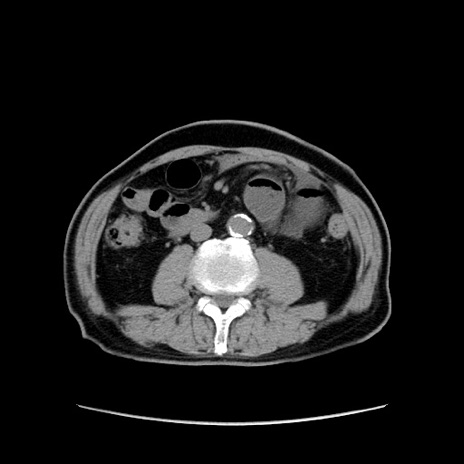

症例24(横断像)

【症例】80歳代男性

【主訴】左側腹部痛、嘔吐

【現病歴】本日早朝より左腹部に痛みあり。昼頃嘔吐認めたため、救急要請。

【既往歴】直腸癌(Mile手術)、胆摘

【身体所見】意識清明、BT 35.9℃、BP 221/93mmHg、SpO2 97%(RA) 、腹部:左ストーマ周囲に限局性の腹部膨隆あり。 膨隆部自発痛・圧痛あり・軟。

【データ】WBC 7700、CRP 0.09